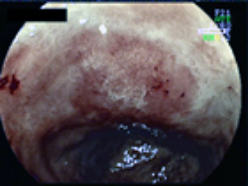

早期胃癌に対するESD

1.胃の幽門部のほとんどを占める早期胃癌。FICE(FUJI intelligent Chromo Endoscopy)・BLI(Blue LASER Imaging)を用いて病変の性質と境界を診断していきます。